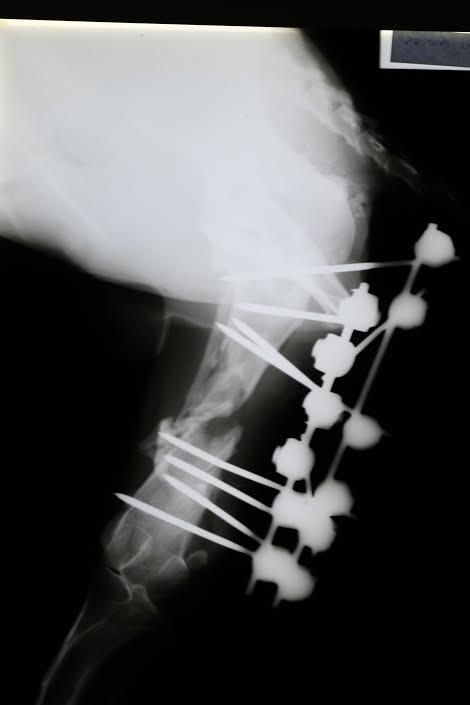

PROCEDIMIENTO QUIRÚRGICO Para la estabilización de la fractura se implanta en el paciente un Fijador Externo Biplanar conformado por dos Hemifijadores o Fijadores Externos Tipo I solidarizados entre sí por barras conectoras (fig.2). Se realiza un abordaje quirúrgico limitado al foco de fractura para intentar lesionar lo menos posible los tejidos blandos periféricos al foco fractuario. La finalidad de este abordaje se limita a valorar la viabilidad de los fragmentos óseos y asegurar la longitud y alineación del fémur, no buscando la reducción anatómica de los fragmentos. EVOLUCIÓN POSTOPERATORIA -15 días postquirúrgicos: El paciente, en posición estática, apoya el pié en el suelo sin carga de peso, presentando una orientación completamente normal del mismo.

Fig 2